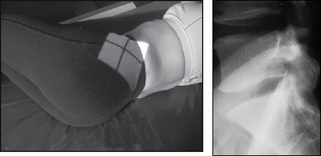

CERVICOTHORACIC

image

Projection: SWIMMER’s

Centring Point: To a level just above the shoulder remote from the cassette. Horizontal central ray

Points to consider

Technique

image Remember to set the exposure before positioning

image Exposure must penetrate the shoulder region

image Do not rotate the thorax unless an oblique projection is required

image Exposure on arrested respiration

Radiological assessment

image Check that each intervertebral joint space is consistent

image Shoulders should be seen separated from each other

image All vertebral bodies should be rectangular – any variation may be due to trauma

image Must include from C5 to T5

Swimmer’s

Patient erect

Shoulder is placed against the erect bucky

Arm nearest the cassette is raised and folded over the head

Arm furthest from the cassette is depressed as far as possible

Median sagittal plane is parallel to the cassette

Collimation

To include: SUPERIORLY: Body C5

INFERIORLY: Body T5

ANTERIORLY: Anterior clavicles

POSTERIORLY: Posterior ribs